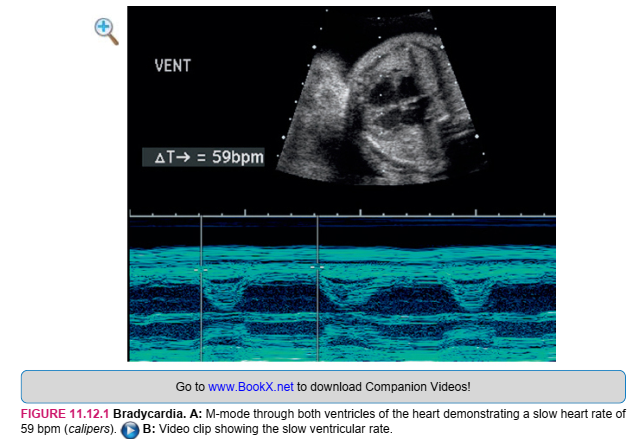

SONOGRAPHY

An abnormal cardiac rhythm can be seen with real-time sonography. M-mode sonography is used to document and characterize the arrhythmia because it can quantify atrial and ventricular rates separately. With bradycardia, the heart rate is abnormally slow, less than 110 beats per minute (bpm) in the second and third trimesters (Figure 11.12.1). With atrioventricular heart block, there is dissociation between the atrial beats and the ventricular beats, with the atria typically beating more rapidly than the ventricles (Figure 11.12.2). With supraventricular tachycardia, the heart rate is faster than normal, more than 180 bpm (Figure 11.12.3). If the tachycardia leads to hydrops, pericardial effusion, pleural effusions, ascites, and/or skin thickening will be present. With atrial flutter, the atrial rate is very fast, usually more than 300 bpm. The atrial rate is even faster (more than 400 bpm) with atrial fibrillation. With atrial flutter or fibrillation, the ventricular rate is usually slower than the atrial rate due to incomplete conduction (Figure 11.12.4).